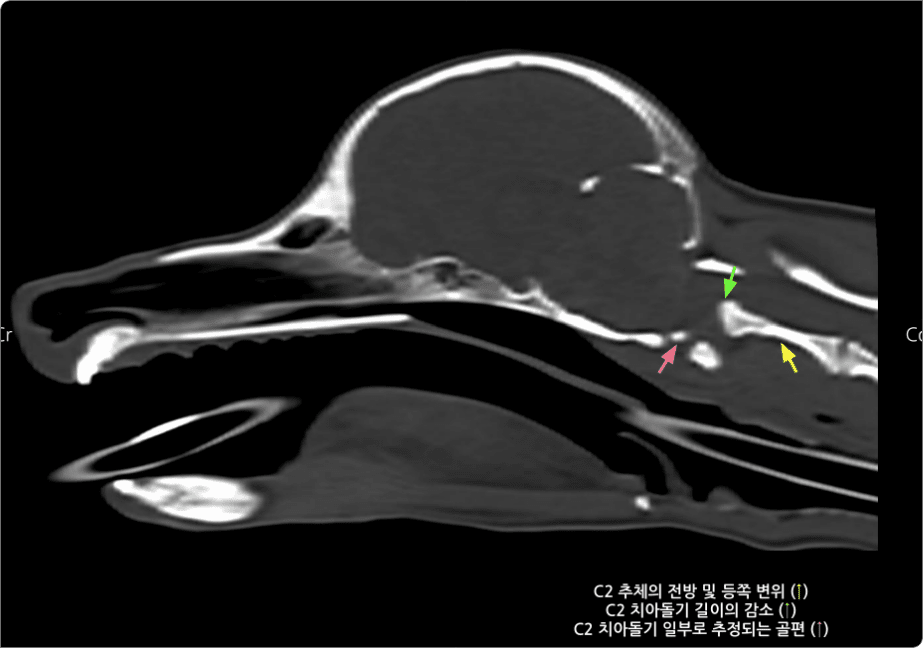

1번 경추(고리뼈)와 2번 경추(중쇠뼈) 연결이 불안정해

척수 신경을 압박하는 질환.

경부 통증과 사지 마비 같은 신경 증상을 유발하며,

만성화 시 영구적 장애가 발생할 수 있음.